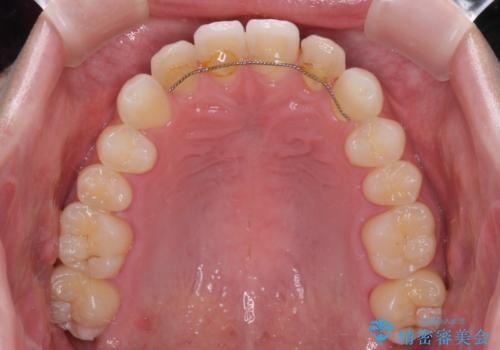

- 前歯のラミネートベニアの不自然な色合いを気にして来院された患者様です。

矯正治療後戻り防止のワイヤー周りにむし歯があったため、オールセラミッククラウンにて補綴することとしました。